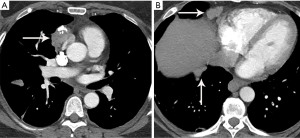

Thymic carcinoma and thymic neuroendocrine tumors have similar imaging characteristics which may often overlap with the more aggressive histologies of thymoma, such as B3 thymoma. Thymic carcinomas and neuroendocrine tumors commonly present as large prevascular masses with irregular or poorly marginated borders, areas of necrosis or cystic change, and hemorrhage. Compared with thymomas, there is a greater incidence of local invasion (1) (Figures 2,11). Pleural or pericardial nodules, pleural effusion, and distant metastasis are more commonly seen with thymic carcinoma or thymic neuroendocrine tumor than thymoma (Figure 12). More aggressive thymic epithelial tumors can invade or compress the SVC resulting in SVC syndrome. This is a clinical syndrome marked by swelling of the neck, face, and upper extremities, with associated cough, headache, and shortness of breath. Pleural metastatic disease, which is more common in thymic carcinoma and thymic neuroendocrine carcinoma, generally consists of small enhancing pleural nodules or areas of enhancing pleural thickening. These are generally adequately assessed with thin-slice contrast-enhanced CT, although, contrast-enhanced MRI and PET/CT can be of additional benefit in questionable cases.

Thymic carcinoma and neuroendocrine tumor/carcinoid